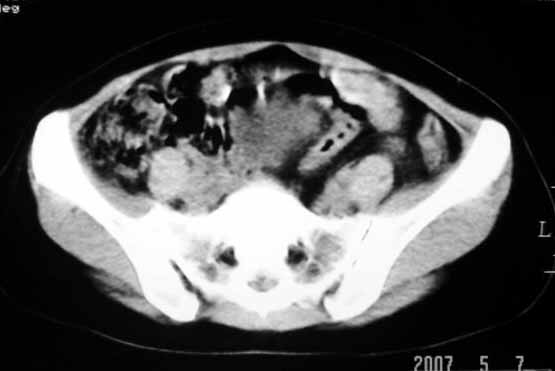

标题: CT8123:女46岁,左下腹胀痛不适1月,以前曾有月经过多史,现已 [打印本页]

标题: CT8123:女46岁,左下腹胀痛不适1月,以前曾有月经过多史,现已

考虑子宫们内膜癌并右侧腹股沟淋巴结转移

考虑子宫肌瘤(变性)或子宫腺肌病,不排除内膜ca可能,不增强建议结合mri或b超检查。

子宫们内膜癌或子宫颈癌体部浸润并右侧腹股沟淋巴结转移

考虑子宫肌瘤,不排除子宫内膜ca可能,不增强建议结合b超检查。